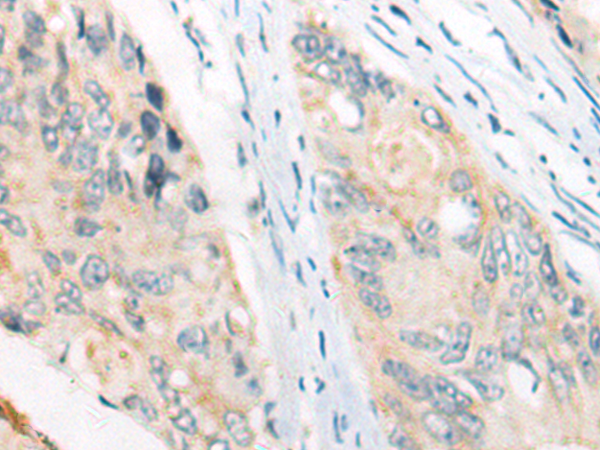

分类: 科研抗体货号: P13209别名: FCC1; COCA1; HNPCC; LCFS2; HNPCC1应用: WB,IHC反应种属: Human, Mouse